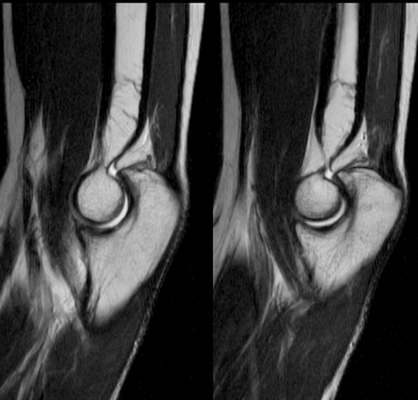

МРТ мышц и сухожилий локтевого сустава во фронтальной поверхности в норме

Локтевой сустав (МРТ анатомия)

Описание исследования 1 - головка лучевой кости 2 - венечный отросток локтевой кости 3 - локтевая кость 4 - локтевой отросток 5 - сухожилие трехглавой мышцы 6 - медиальная коллатеральная связка локтевого сустава 7 - лучевая коллатеральная связка локтевого сустава 8 - латеральная коллатеральная связка 9 - латеральный надмыщелок плечевой кости 10 - сухожилие двуглавой мышцы плеча 11 - плечевая мышца 12 - длинный лучевой разгибатель запястья 13 - блок плечевой кости 14 - локтевая мышца 15 - глубокий сгибатель пальцев 16 - локтевой сгибатель запястья 17 - трехглавая мышца 18 - кольцевидная связка лучевой кости 19 - двуглавая мышца плеча 20 - супинатор 21 - плечелучевая мышца 22 - круглый пронатор 23 - разгибатель пальцев 24 - лучевой сгибатель запястья 25 - поверхностный сгибатель пальцев 26 - локтевой нерв 27 - локтевой сгибатель запястья 28 - короткий лучевой разгибатель запястья 29 - общее сухожилие разгибателей 30 - общее сухожилие сгибателей и круглого пронатора 31 - бугристость лучевой кости 32 - головка плечевой кости 33 - медиальный надмыщелок плечевой кости 34 - гребень супинатора 35 - трапециевидная связка (lacertus fibrosus) 36 - наружная головка трехглавой мышцы плеча 37 - длинная головка трехглавой мышцы плеча 38 - медиальная головка трехглавой мышцы плеча 39 - общее сухожилие сгибателей